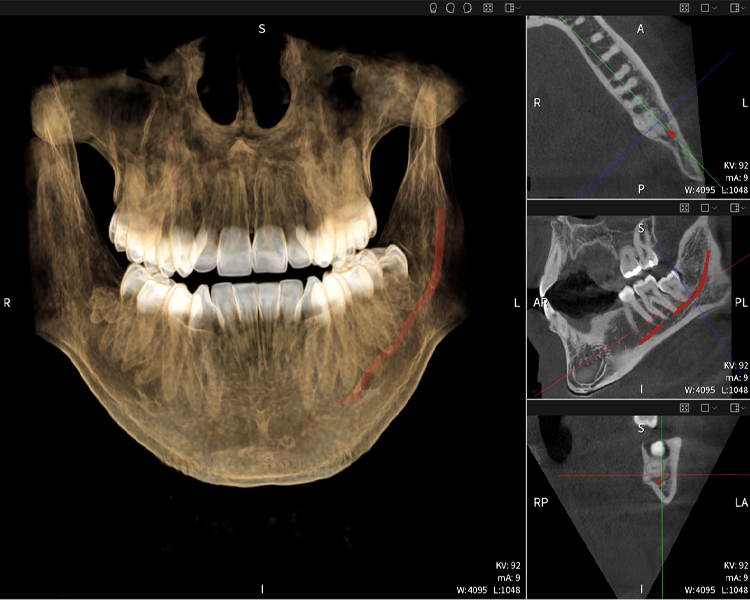

Nachstehend finden Sie einen Fall von Dr. med. dent. Oliver A. Centrella, in dem die CBCT-Aufnahmen mit Seethrough Max entscheidende Informationen zur komplexen Anatomie sowie zur kritischen Beziehung zwischen den Weisheitszähnen und dem Nervus alveolaris inferior lieferten. Bei diesem Fall besteht eine Indikation zur chirurgischen Entfernung der Weisheitszähne.

Abbildungen b–d zeigen verschiedene Ansichten einer 3D-Rekonstruktion des Unterkiefers und bieten eine umfassende Übersicht über die Anatomie des Unterkiefers, die Lage der Nerven im Verhältnis zu den Zähnen und ermöglichen die Beurteilung der Zahnsymmetrie und Ausrichtung.